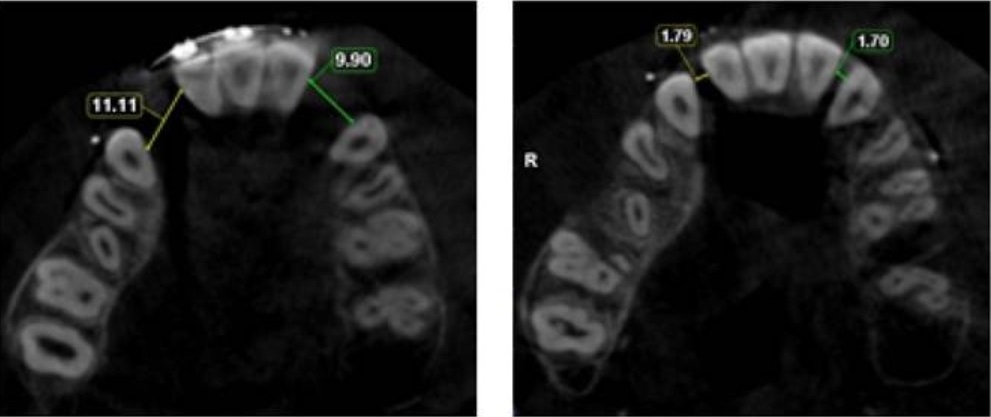

Con arco 0,017 x 0,025 de acero en arcada inferior, se colocan mini implantes mandibulares de 2 x 12 mm para corregir la mordida cruzada anterior. En la arcada superior, el tratamiento ortodóntico avanza hasta corregir la mordida cruzada en cuatro meses. Una vez alcanzados los arcos de acero 0,017 x 0,025, las fisuras alveolo-palatinas miden 11 mm (derecha) y 10 mm (izquierda) (Figura 1), por lo que se decide realizar transportación ósea alveolar bilateral.

Tras dos semanas, se observa la reducción de las fisuras y la elongación de tejidos blandos, fijando los segmentos con ligaduras metálicas y manteniéndolos en contención por 4 meses. Un nuevo estudio con tomografía Cone Beam muestra avances significativos: la fisura derecha disminuye de 11,11 mm a 1,79 mm y la izquierda de 9,90 mm a 1,70 mm, con adecuada formación ósea en ambas zonas. Se detecta una lesión menor en la raíz palatina del primer molar superior derecho, sin comprometer la pulpa ni presentar complicaciones posteriores (Figura 3).